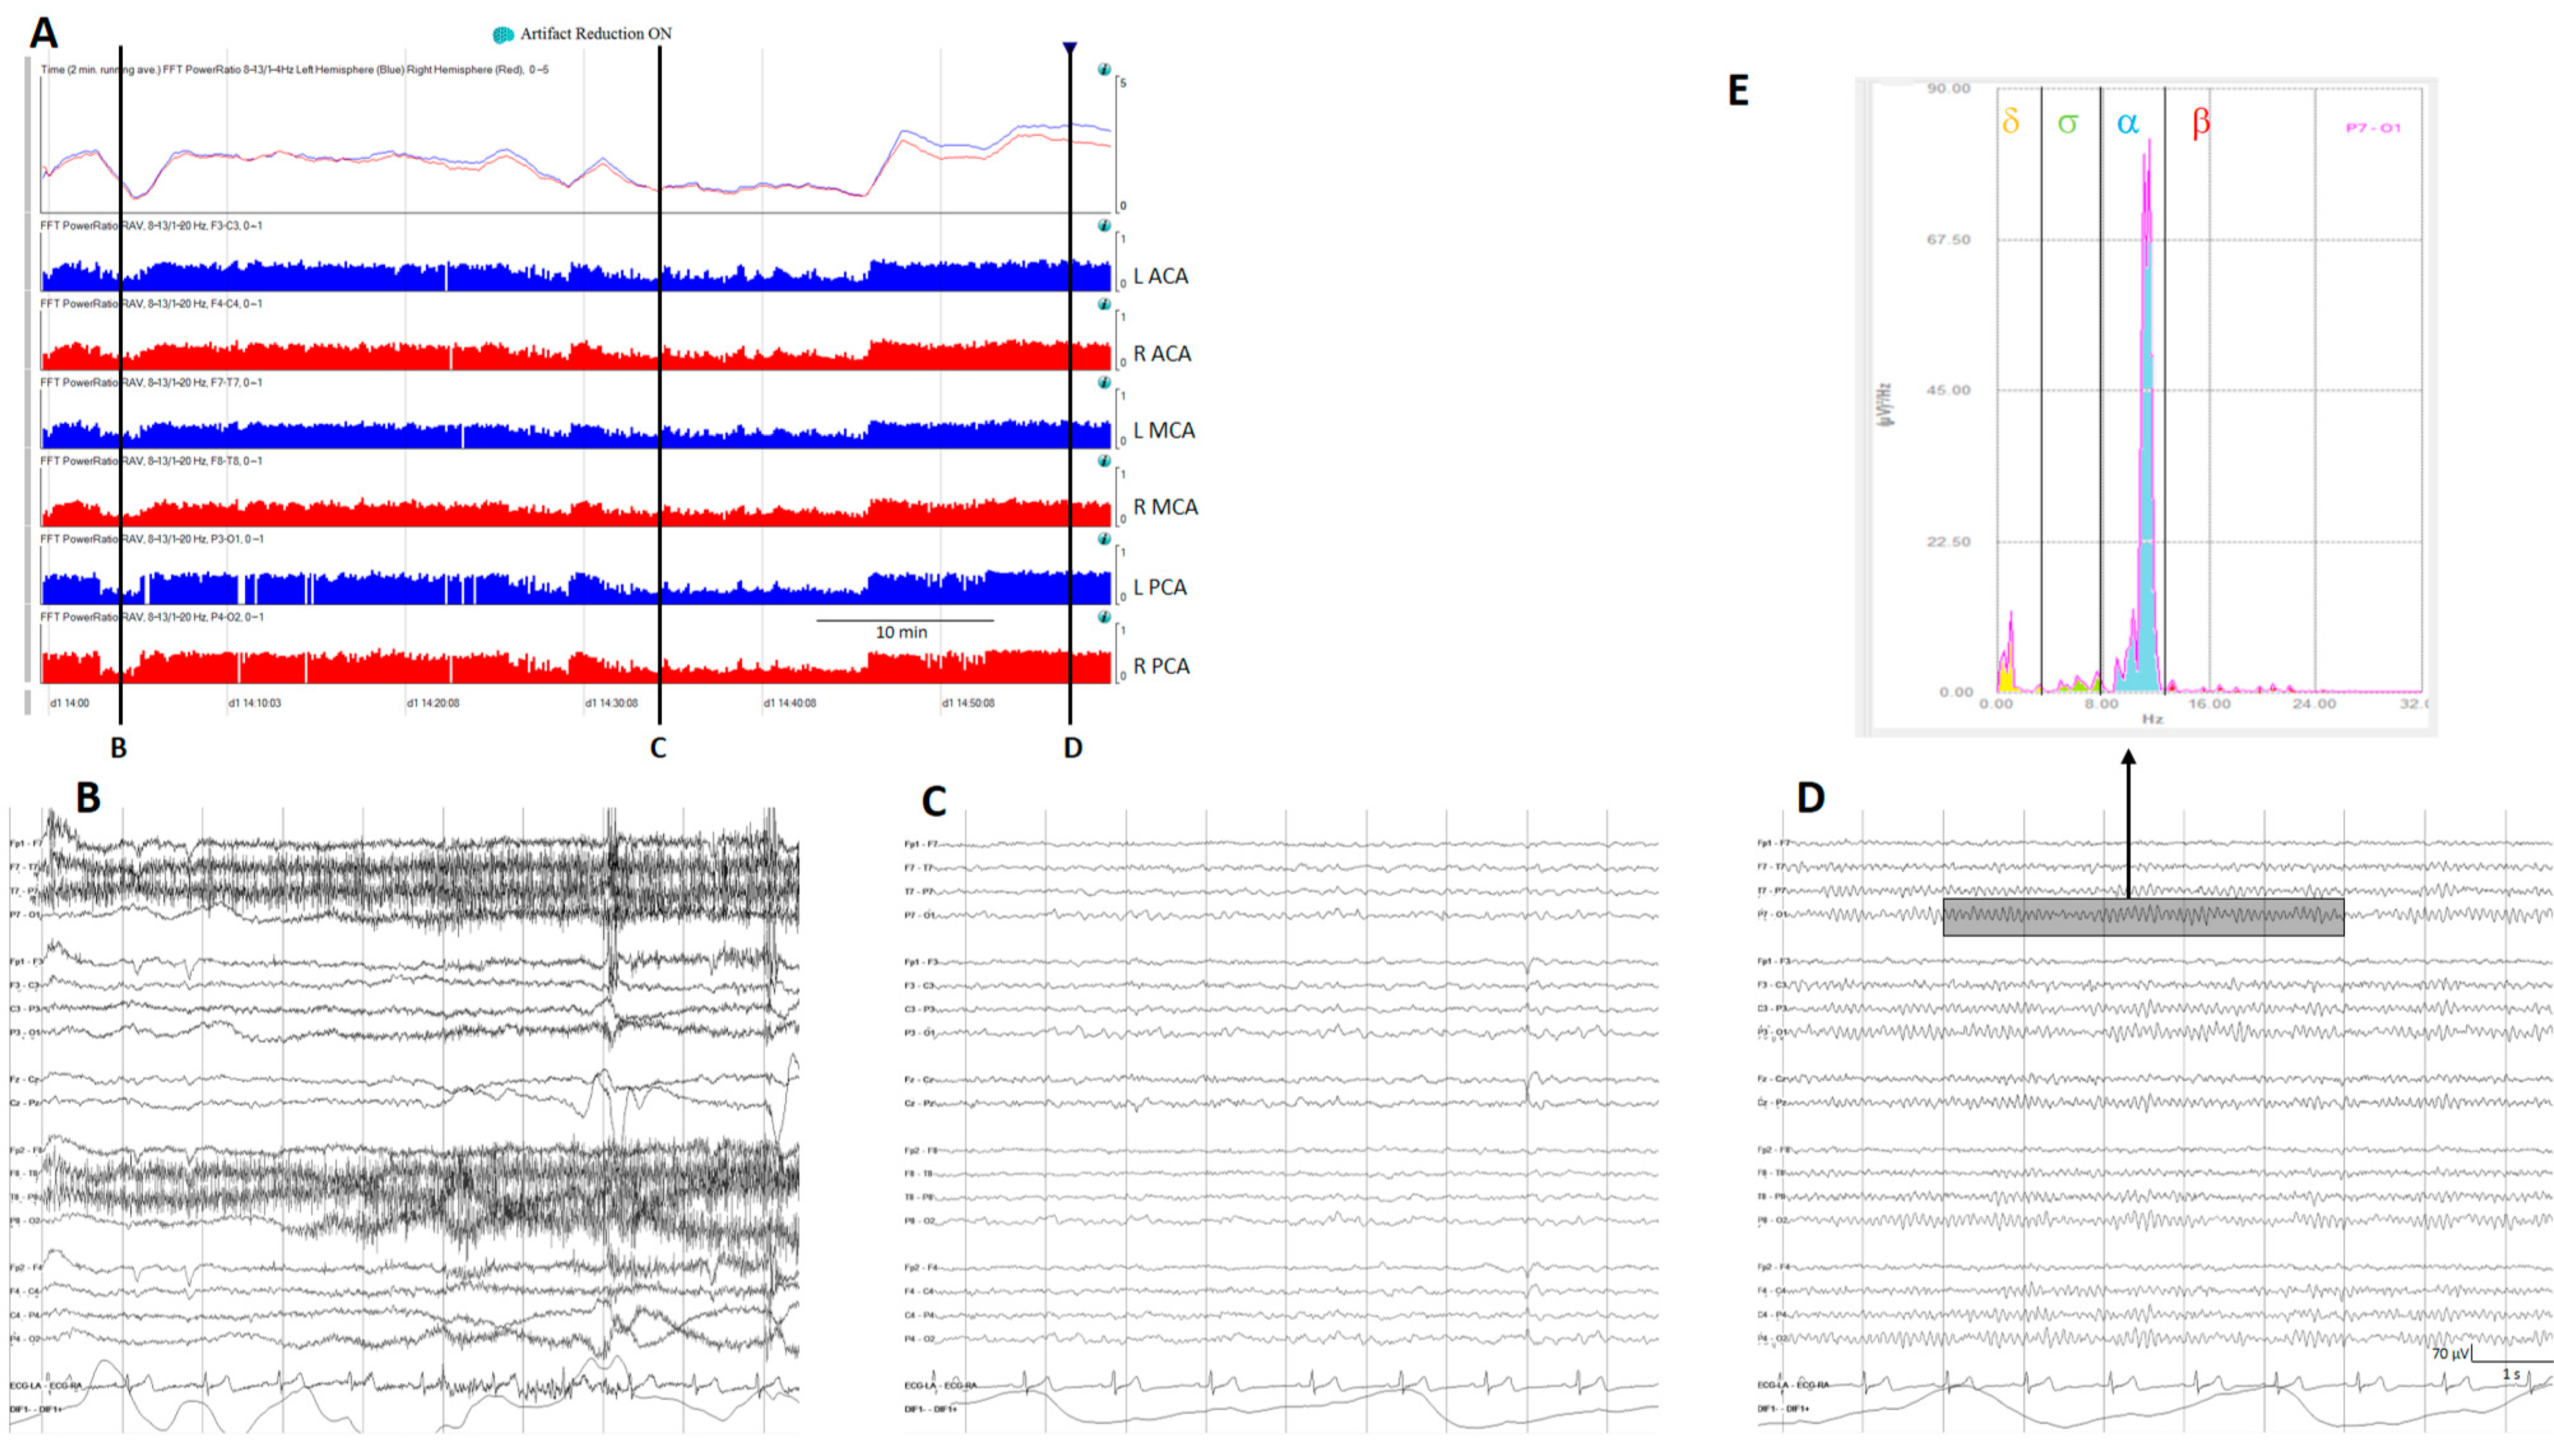

Figure 4.

(A) A qEEG panel from a normal subject; from top to bottom: ADR (alpha-to-delta ratio) from the right and left hemispheres; RAV (relative alpha variability) from the major vascular territories: anterior cerebral artery (ACA), middle cerebral artery (MCA), posterior cerebral artery (PCA). (B) Awake with eyes open, (C) sleeping, and (D) awake with eyes closed. Note the variability on the ADR and on the RAV in a normal subject. (E) Fast Fourier transform from a period of EEG (rectangle on (D)); the power of each frequency band is shown in a different color. To calculate ADR, the power of alpha frequencies (8–13 Hz) is divided by the power of delta frequencies (1–4 Hz). To calculate RAV, the alpha power (8–13 Hz) is divided by the total power (1–20 Hz). ADR: alpha-to-delta ratio. RAVL relative alpha variability. L: left, R: right.

Relative power, another time domain measure, calculates the ratio of power for a specific frequency of interest to total power; the most used is relative alpha variability (RAV), assessing variability in alpha power relative to total power. In normal subjects, RAV exhibits significant variability (see Figure 4), which diminishes in patients at risk of delayed cerebral ischemia (DCI) after aneurysmal subarachnoid hemorrhage (aSAH). In this situation, RAV is visually graded from 4 to 1. Four means excellent variability with excursions (variability) from baseline occurring once per hour or of greater than 15% (visually has the appearance of skyscrapers), 3 is good (excursions of 10% at least every 4 h), 2 is fair (only small or infrequent excursions), and 1 is poor (no excursions greater than 2%) [26].

The power ratio is one of the trends that generates more interest in evaluating aSAH patients at risk of DCI. Power ratio refers to the ratio of power of two different frequency bands; for example, the alpha-to-delta ratio (ADR). Many other ratios between frequency bands are feasible and in some clinical situations useful [13,25,27].